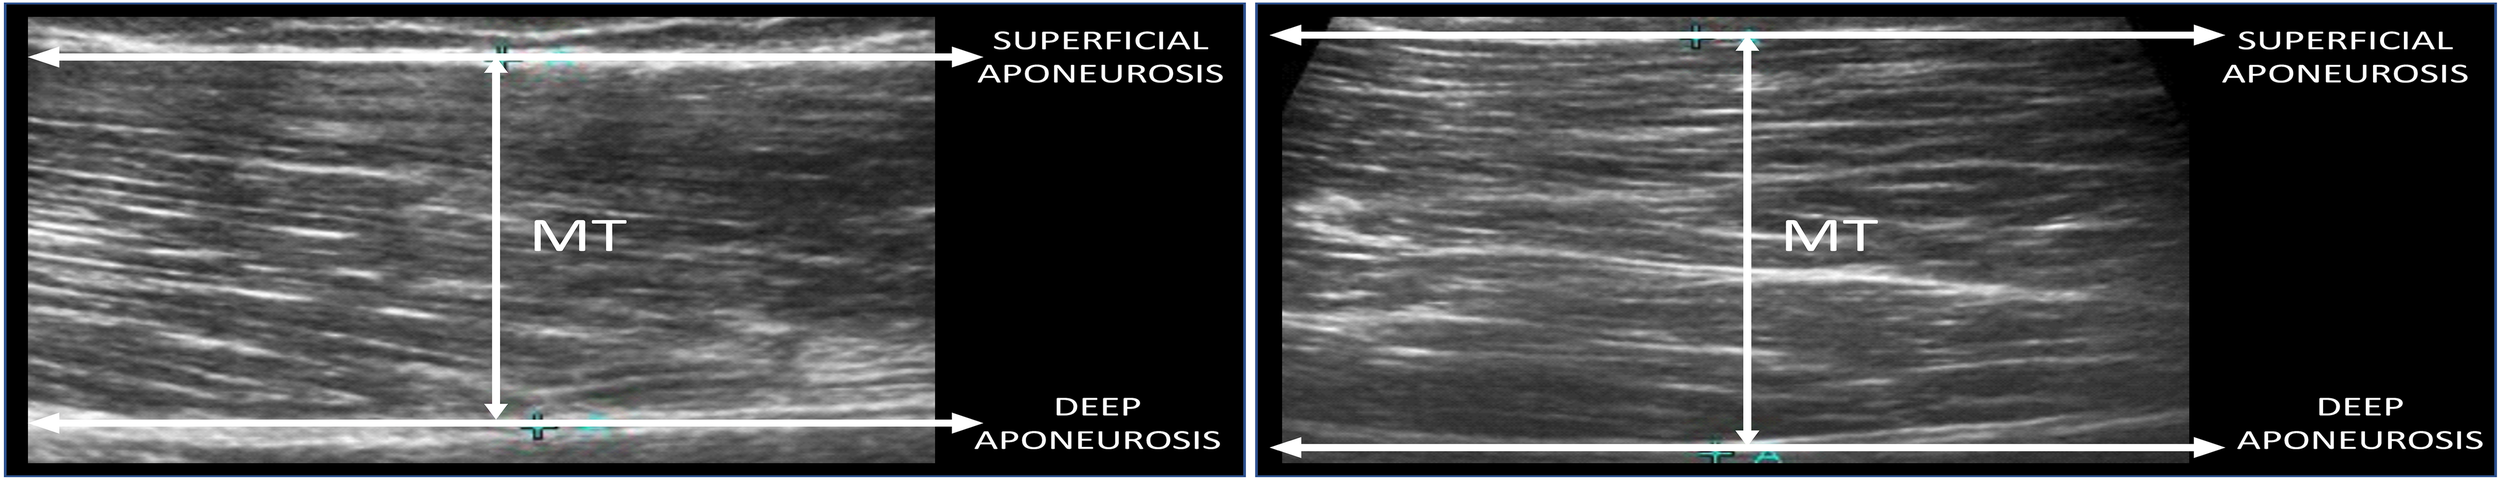

Muscle Thickness

Before and after the RT programs, muscle thickness from quadriceps femoris (two portions per muscle) were evaluated using ultrasound images gathered from a blinded, experienced physician using ultrasound mode B (Toshiba Aplio Mx, SSA-780 A, Toshiba Medical System®), and a probe of 100 mm, set to 10–15 MHz. Resting images were collected at a specific joint angle (150°), corresponding to almost full knee extension (180°). Participants were positioned supine on a stretcher, where they rested for 20 min. After this interval, the transducer was aligned to the fascicular plane to visualize the fascicules on the ultrasound monitor. After the registering of the quadriceps images, the participant moved to prone position to measure gluteus maximus thickness. When the quality of the image was deemed to be satisfactory, the image was saved to the hard drive, and muscle thickness dimensions were determined by measuring the distance between the deep and superficial aponeuroses (Figure 2). All participants were advised to avoid alcoholic drinks and exercise 72 h before the exams. Ultrasound measures were taken 72 h after the last training session to avoid interference. The precision parameters provided by the manufacturer are: image depth scale, track to 280 mm (<±5% or <1 mm, if <20 mm).

FIGURE 2

Example of ultrasound image showing the cross-cutting scans of the vastus lateralis muscle – distal part, at 35% of the length of the thigh (left) and gluteus maximus (right). MT, muscle thickness.

The measures were taken distally and proximally to the quadriceps muscles to evaluate possible non-homogeneous alterations in muscle thickness. The measured regions were adopted according to the recommendations from Ema et al. (2013), excluding gluteus maximus.